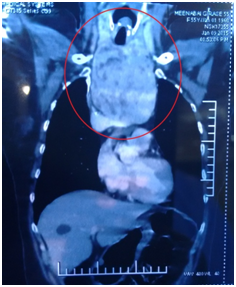

A 55 year old reported to our cancer centre with a chief complaint of difficulty in breathing and eating from 2 years. General examination was insignificant. Local examination revealed a diffuse swelling of left lobe of thyroid (Figure 1). Her medical history revealed hyperthyroidism from 2 years. A provisional diagnosis of Thyroid swelling was made. Radiological examination was done. Computed tomography of neck revealed 12 x 8 x 7cm retrosternal mass arising from left lobe of thyroid with tracheal compression (Figure 2). There was no cervical lymphadenopathy. Thyroid function test (T3, T4 and TSH) were done. T3 was 2.11nmol/l, T4 was 228.86nmol/l and TSH was less than 0.06uIU/Ml. Fine needle aspiration of the lesion gave a final diagnosis of nodular colloid goitre with cystic changes. Since T4 was high, patient was started on Tab Neomarkazole 2.5mg, Tab Inderal 80mg and Lugol Iodine solution orally for 5 days to avoid Thyrotoxicosis. After 5 days T3 was 0.98nmol/L, T4 was 180.36nmol/L and TSH was less than 0.05Uiu/Ml. Patient was taken for surgery. Fibreoptic laryngoscopy was done to visualize the tracheal patency. Awake intubation was done. General anesthesia was administered. Necklace incision was given 2cm above the sternum. Strap muscles were dissected. Thyroid gland was exposed. First left thyroid gland was mobilized followed by right thyroid gland. Bilateral recurrent laryngeal nerve was identified and preserved (Figure 3). The left thyroid mass was dissected. Sternotomy was done to enucleate the retrosternal mass from anterior mediastinum. Thyroid gland along with retrosternal mass was excised (Figure 4). Homeostasis was achieved. Drains were kept and closure was done in layers. Postoperatively patient was started on Tab Neomaracazole 2.5mg and Tab Inderal 80mg. Postoperative T4 was 145nmol/L. Patient was discharged on 4th postoperative day and patient is doing fine in 5 months of follow-up with no complications.

Figure 2 Computed tomography of neck revealed 12 x 8 x 7cm retrosternal mass arising from left lobe of thyroid with tracheal compression.